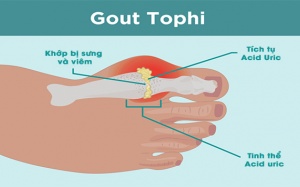

Hạt tophi là những khối tinh thể urat, xuất hiện xung quanh khớp, thường gặp ở những người mắc bệnh gout mạn tính. Nếu không được xử lý kịp thời, hạt tophi có thể bị vỡ ra gây...

Hạt tophi là biến chứng hay gặp ở người bệnh gout lâu năm. Nếu hạt tophi có kích thước lớn và không được điều trị kịp thời sẽ gây nhiễm trùng, lở loét, thậm chí biến dạng khớp...